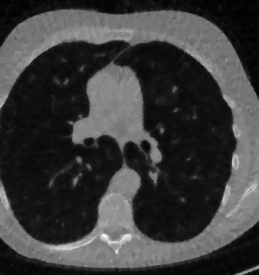

The considered images are pixel reconstructions of human abdomen, computed from full-dose acquisitions. In Figure 2 we depict one image with two zooms-in highlighting areas with different anatomical structures, such as pulmonary details, sections of ribs and low-contrast inter-costal muscles.

In all the experiments reported in 5.1, we have used the images from the data set as ground truth references.

Here we present the results of RISING applied to the Mayo data set introduced in paragraph 4.1. As previously mentioned, we consider two sparse-view CT geometries, namely and . In Figure 4 we report the results for the protocol, achieved on one image of our test set. The top-left image represents the reconstruction. Even if only a small number of iterations are performed, the main structures of the abdomen are visible; however, the image is still blurry. In the image, shown in the upper-right corner, we notice that the TV regularizer has acted to totally eliminate the artifacts and noise, improving the uniformity of the image in the inner structures. When compared to the ground-truth solution in Figure 2, the contours of the details in appear slightly jagged, differently from where they are neat but, usually, corrupted by artifacts. The bottom row of Figure 4 shows the two and images, respectively from left to right. It is evident that has retrieved many details but it presents noisy components, reflecting the features of its target image . Our solution is less corrupted, since the low-contrast regions are correctly preserved and the noise is not visible. These observations are confirmed by Figure 5, which plots the intensity profiles taken over the red line in the second crop (Figure 2). In our approach (on the right) the CNN has accurately learnt the map of (8) and the red profile mostly overlaps the black one. On the contrary, the profile (on the left) is more distant from its target reference.